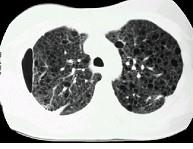

问题 女,33岁,气短伴咳嗽2周,CT检查如图,最可能的诊断为 ( )

选项 A.肺间质纤维化 B.肺淋巴管肌瘤病 C.慢性支气管炎并感染 D.硅沉着病 E.肺囊肿并感染

答案 B